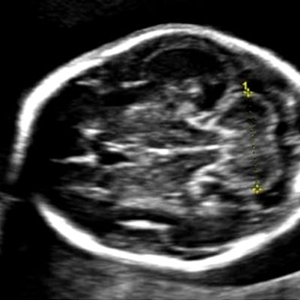

Fetal Neurosonogram A specialist examination of the fetal brain is recommended in cases of: suspected fetal intracranial abnormalityprevious baby with intracranial abnormality